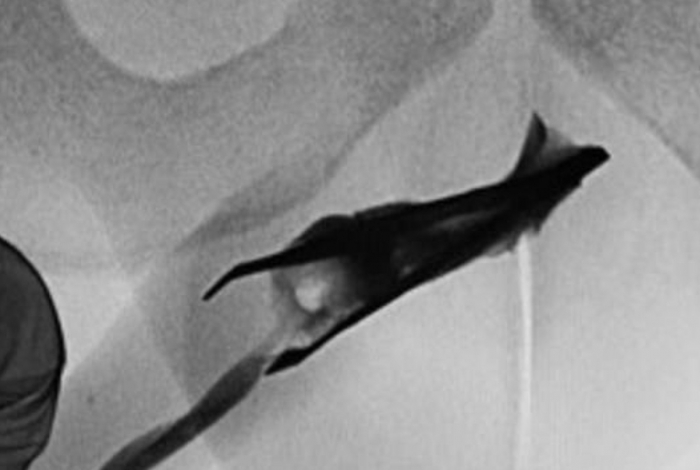

Um homem de 22 anos precisou passar por um procedimento médico após ficar por quatro anos com uma pinça de oito centímetros alojada na uretra na Arábia Saudita. O caso foi reportado pelo jornal médico Urology Case Reports.

Um raio-x foi realizado e o homem foi levado para a mesa cirúrgica. No local, ele recebeu anestesia geral e os médicos puderam analisar melhor a posição da pinça. Os profissionais aplicaram "pressão" no pênis do rapaz para fechar a pinça e a retiraram com um fórceps.

Objeto metálico estava alojado hà quatro anos no membro inferiordo rapaz (Urology Medicine Reports / Divulgação)